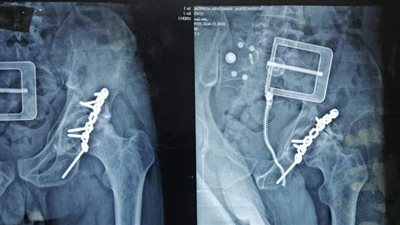

اعلن الدكتور سعد مكي وكيل وزارة الصحة بالدقهلية عن نجاح فريق طبي بإنهاء معاناة طفلة تبلغ من العمر 11 عاما كانت تعاني من إفراط مستمر في نشاط الغدد العرقية لليدين نتيجة وجود خلل في التحكم العصبي للعصب السمبثاوي المسئول عن افراز العرق اللازم لتنظيم درجة حرارة الجسم والذي أثر سلبا على ممارستها للحياة الطبيعيه اليومية .